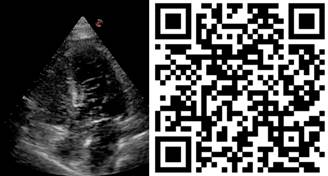

Por el soplo en la exploración física y el probable defecto septal, se sospecha de shunt cardiaco, por lo que se baja PEEP a 10 cmH2O evidenciando mejoría de la saturación logrando disminuir FiO2 a 70%, y bajar dosis de vasopresor. Se corrobora shunt cardiaco tras realizar prueba de burbujas, al evidenciar un gran paso de éstas a cavidades izquierdas (Figura 2), por lo que se procede a realizar mediciones más avanzadas; fracción de eyección del ventrículo izquierdo (FEVI) 86%, relación ventrículo derecho (VD) - VI de 0.57, sin datos de insuficiencia del VD, hipertensión pulmonar leve por presión media de la arteria pulmonar de 24.7 mmHg por método de Chemla , presión de la aurícula derecha de 20 mmHg, GC de 6.3 L/min, índice cardiaco (IC) de 3.5 L/min/m2, resistencias vasculares pulmonares (RVP) elevadas de 2.7 unidades Wood mediante ultrasonido y formula descrita por Abbas.8 Por lo anterior, se presume que el deterioro hemodinámico y respiratorio de la paciente era debido a la VPP, y el consecuente aumento o aparición de shunt intracardiaco.

Figura 2: Prueba de burbujas con PEEP de 10 cmH2O. La prueba de burbujas o también conocida como prueba de solución salina agitada, se realiza mediante ecocardiografía con contraste de solución salina agitada para detectar cortocircuitos cardiacos. Implica la inyección de una mezcla de solución salina (8-10 mL ) y aire (0.5 mL ), a veces con una pequeña cantidad de sangre, a través de un acceso venoso ya sea central o periférico. En esta imagen vemos un paso importante de burbujas de cavidades derechas a izquierdas tanto a nivel ventricular como auricular, lo que confirma la presencia de shunt dinámico a este nivel de PEEP. V ideo al escanear el código QR.